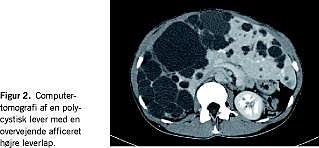

Levercysters forekomst i befolkningen varierer fra ca. 0,1% og helt op til 20% [1, 2]. Den øgede anvendelse af ultralydskanning og computertomografi (CT) har medført hyppigere diagnostik, da nu også de mindre levercyster findes. Prævalensen er fortsat mindre end for nyrescyster, men mellem de to cysteformer er der et sammenfald, som øges med alderen uden signifikante kønsforskelle for de asymptomatiske cysters vedkommende [2], mens de symptomatiske forekommer i forholdet 9:1 hos kvinder og mænd. Simple cyster kommunikerer yderst sjældent med galdevejene, og en arbitrær grænse for intervention har været sat til seks cm (Figur 1 ).